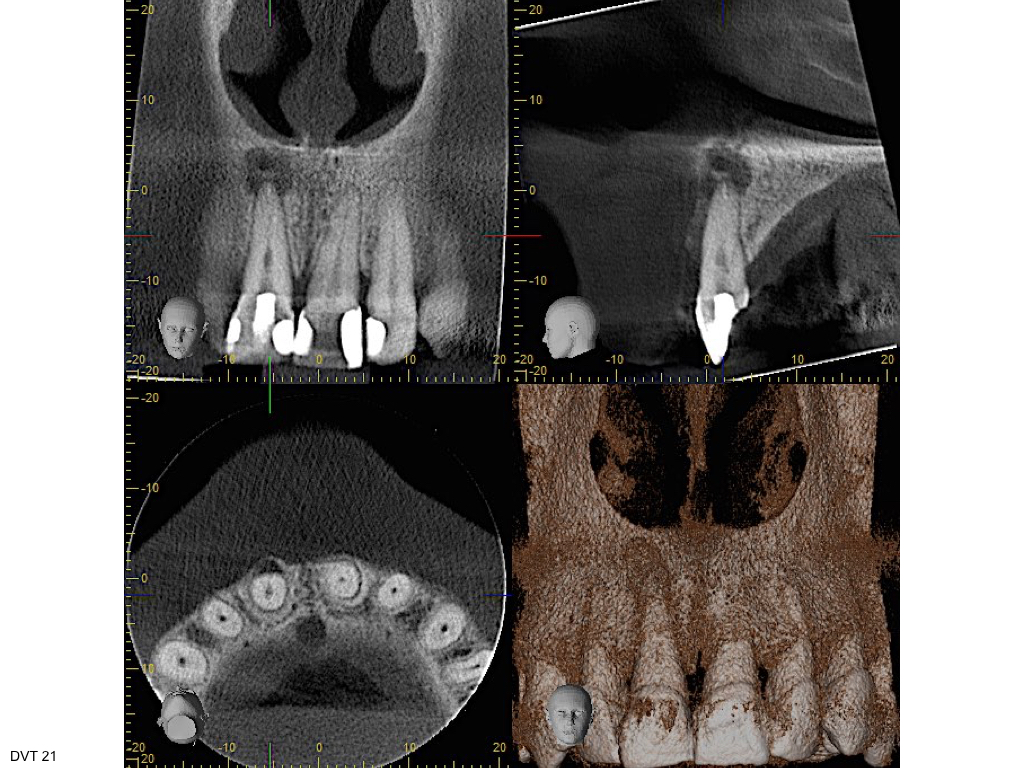

Vorsicht Falle (1) – Infraktur